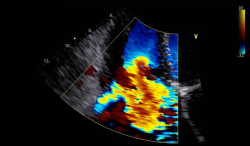

Doppler (PW/CW/Color) – „wann was?“

Farbdoppler Mitralinsuffizienz

Pathologien & Befundung

Klappenvitien, diastolische Funktion, rechter Ventrikel, typische Fallbeispiele.

Klappen – relevante Schweregrade sauber bestimmen